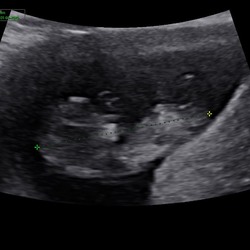

Hoi hoi! Hier 13+4 zwanger en vandaag 13 weken echo gehad. Dit is de enige foto van de zijkant want ons kindje was steeds aan het draaien haha. Heel benieuwd of jullie iets kunnen zien. Groetjes!

Hoi hoi! Hier 13+4 zwanger en vandaag 13 weken echo gehad. Dit is de enige ...